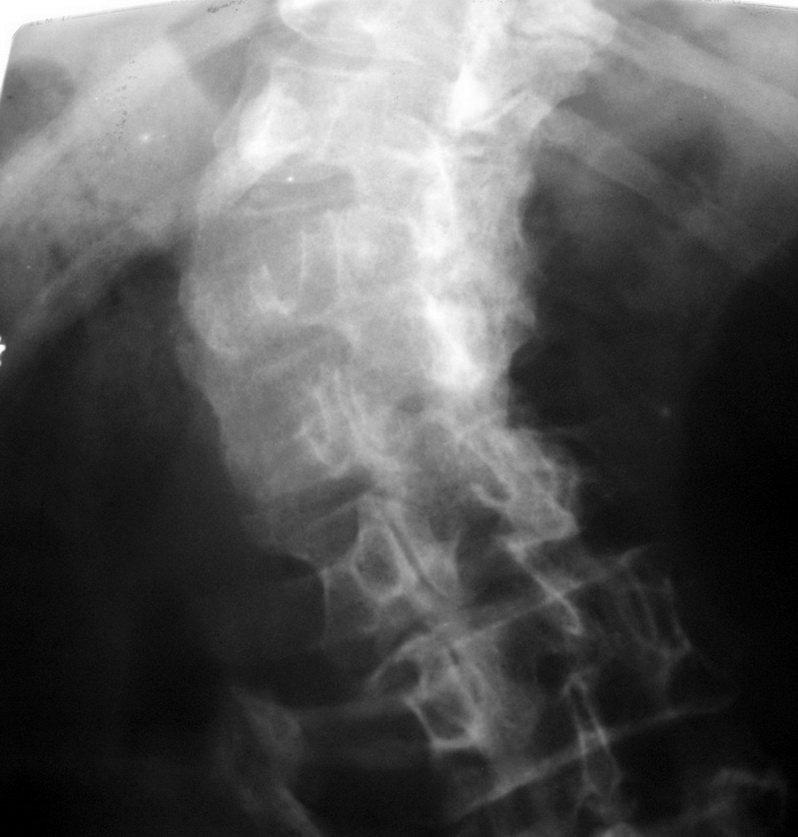

标题: X4179:腰椎会诊

请各位指点。

脊椎侧弯畸形,上面太白,看不清。

考虑:脊柱侧弯,l123看不清,可能有半椎畸形等,查查尿生殖道是否有异常.

脊柱s形侧弯旋转,t12,l1.2看不清.请提供侧位片.

显然上部腰椎已是强直性表现.病因只有结合病史.前面的老师提到畸形性骨炎, 我认为可不考虑,因为没畸形性骨炎的主要表现,即骨体呈增大增宽的破坏和成骨.

脊椎成\"s\"形弯曲,椎体边缘骨质增生改变明显,考虑脊椎侧弯畸形伴退变

脊椎成"s"形弯曲,椎体边缘骨质增生改变明显,考虑脊椎侧弯畸形伴退变